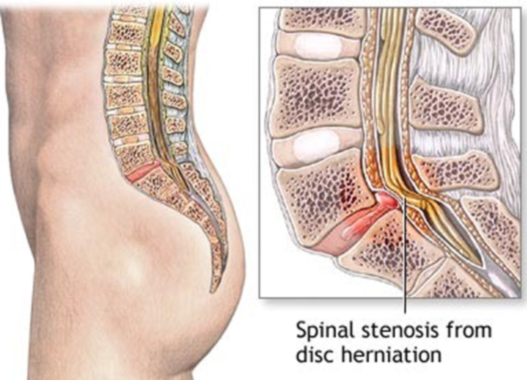

Do you suffer from sharp pains every time you bend? Back pain, of this nature, is often the result of a #herniateddisc or #pinchednerve: both caused by preventable #spinaldisc problems. Before considering drugs/surgery, a chiropractor can help! Book your appointment today!

A #slipdisc occurs when a #spinaldisc bulges out, causing pain, #numbness, or #weakness. Early #treatment can prevent worsening #symptoms. Dr.SrinivasBotla Neurosurgeon and Spine Surgeon YashodaHospitals,Malakpet For More Visit: srideviclinic.com

A #slipdisc occurs when a #spinaldisc bulges out, causing pain, #numbness, or #weakness. Early #treatment can prevent worsening #symptoms. Dr.SrinivasBotla Neurosurgeon and Spine Surgeon YashodaHospitals,Malakpet For More Visit: srideviclinic.com

Do you suffer from sharp pains every time you bend? Back pain, of this nature, is often the result of a #herniateddisc or #pinchednerve: both caused by preventable #spinaldisc problems. Before considering drugs/surgery, a chiropractor can help! Book your appointment today!